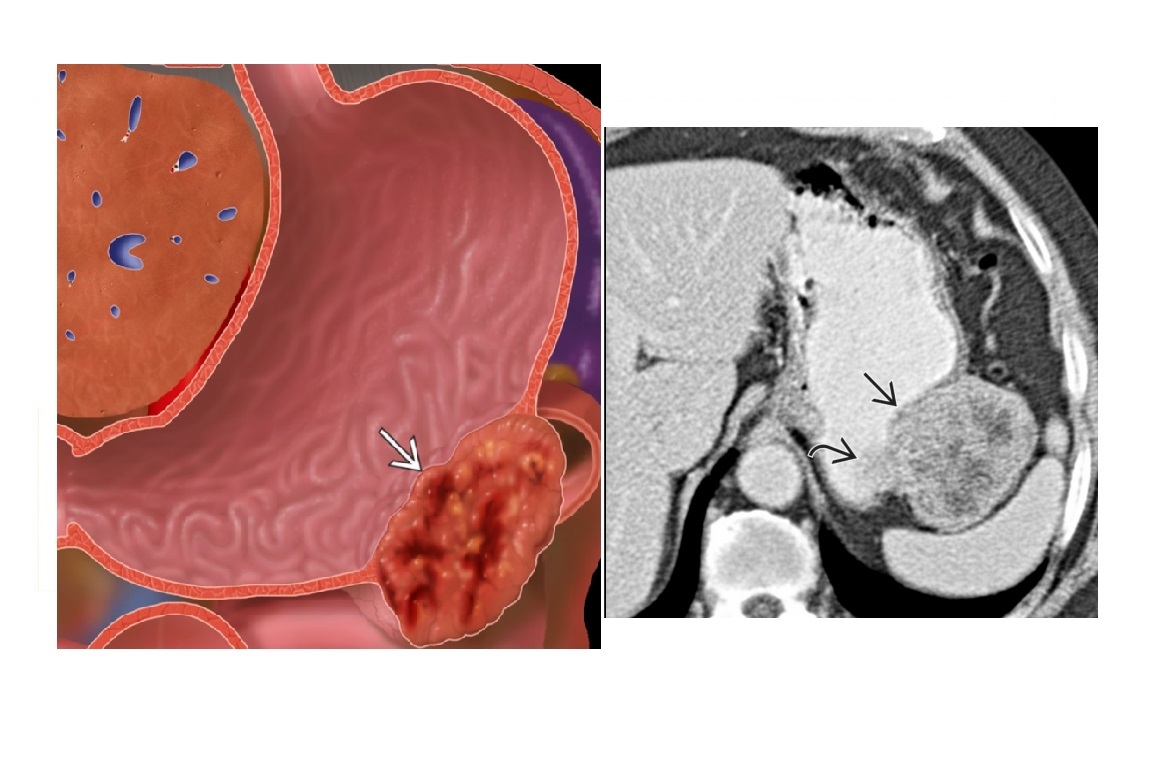

gastric carcinoma

1. Intraluminal mass with no peristalsis through lesion (at fluoroscopy)

- Antral mass causing outlet obstruction

2. Ulcer -

Width > depth, nodular edges

obliteration of surrounding areae gastricae

3. Infiltrative -

Diffuse infiltration of gastric wall; non-peristaltic, non-distensible = **Linitis plastica (leather bottle) ***

**Pseudoachalasia: Fundal carcinoma may destroy myenteric plexus

Oesophageal obstruction, dilated lumen, diminished peristalsis; mistaken for primary achalasia - Pseudo the GE junction doesnt relax

Krukenberg tumor: Metastases to ovaries via peritoneal seeding

Early epigastric nodes